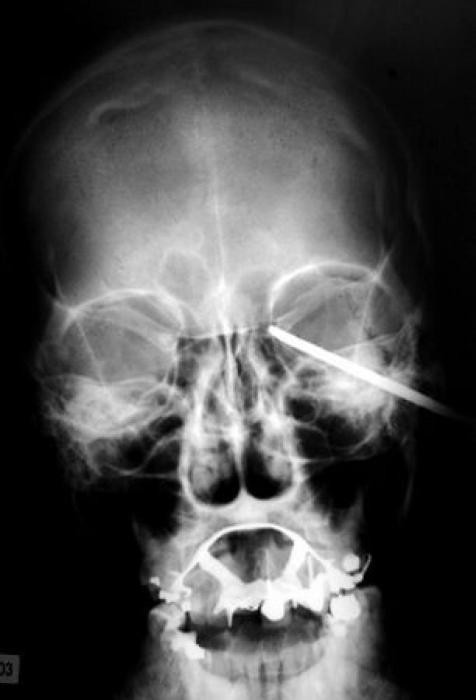

33 radiographies qui prouvent que les gens font des choses douteuses avec leur corps !